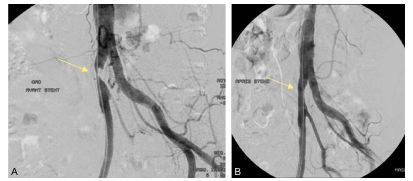

C. Radiologie interventionnelle

Le premier temps de la thérapeutique endovasculaire est l’artériographie qui montre les lésions à traiter et sert de guidage pour l’intervention endovasculaire (figure 38.4A). La dilatation endovasculaire avec un cathéter à ballonnet gonflable est appelée angioplastie percutanée. Quand le résultat de la dilatation est insuffisant, l’angioplastie est complétée par la mise en place d’une endoprothèse (ou stent) par voie endovasculaire (figure 38.4B). Enfin, si les sténoses sont trop nombreuses et/ou trop étendues pour bénéficier d’angioplastie, le patient aura une revascularisation chirurgicale (pontage).

Fig. 38.4 Exemple d’angioplastie percutanée d’une sténose de l’artère iliaque commune droite.

L’artériographie en premier temps de l’angioplastie montre la lésion (A) et l’artériographie après la poste du stent montre le rétablissement du diamètre artériel (B).

Source : CERF, CNEBMN, 2022.